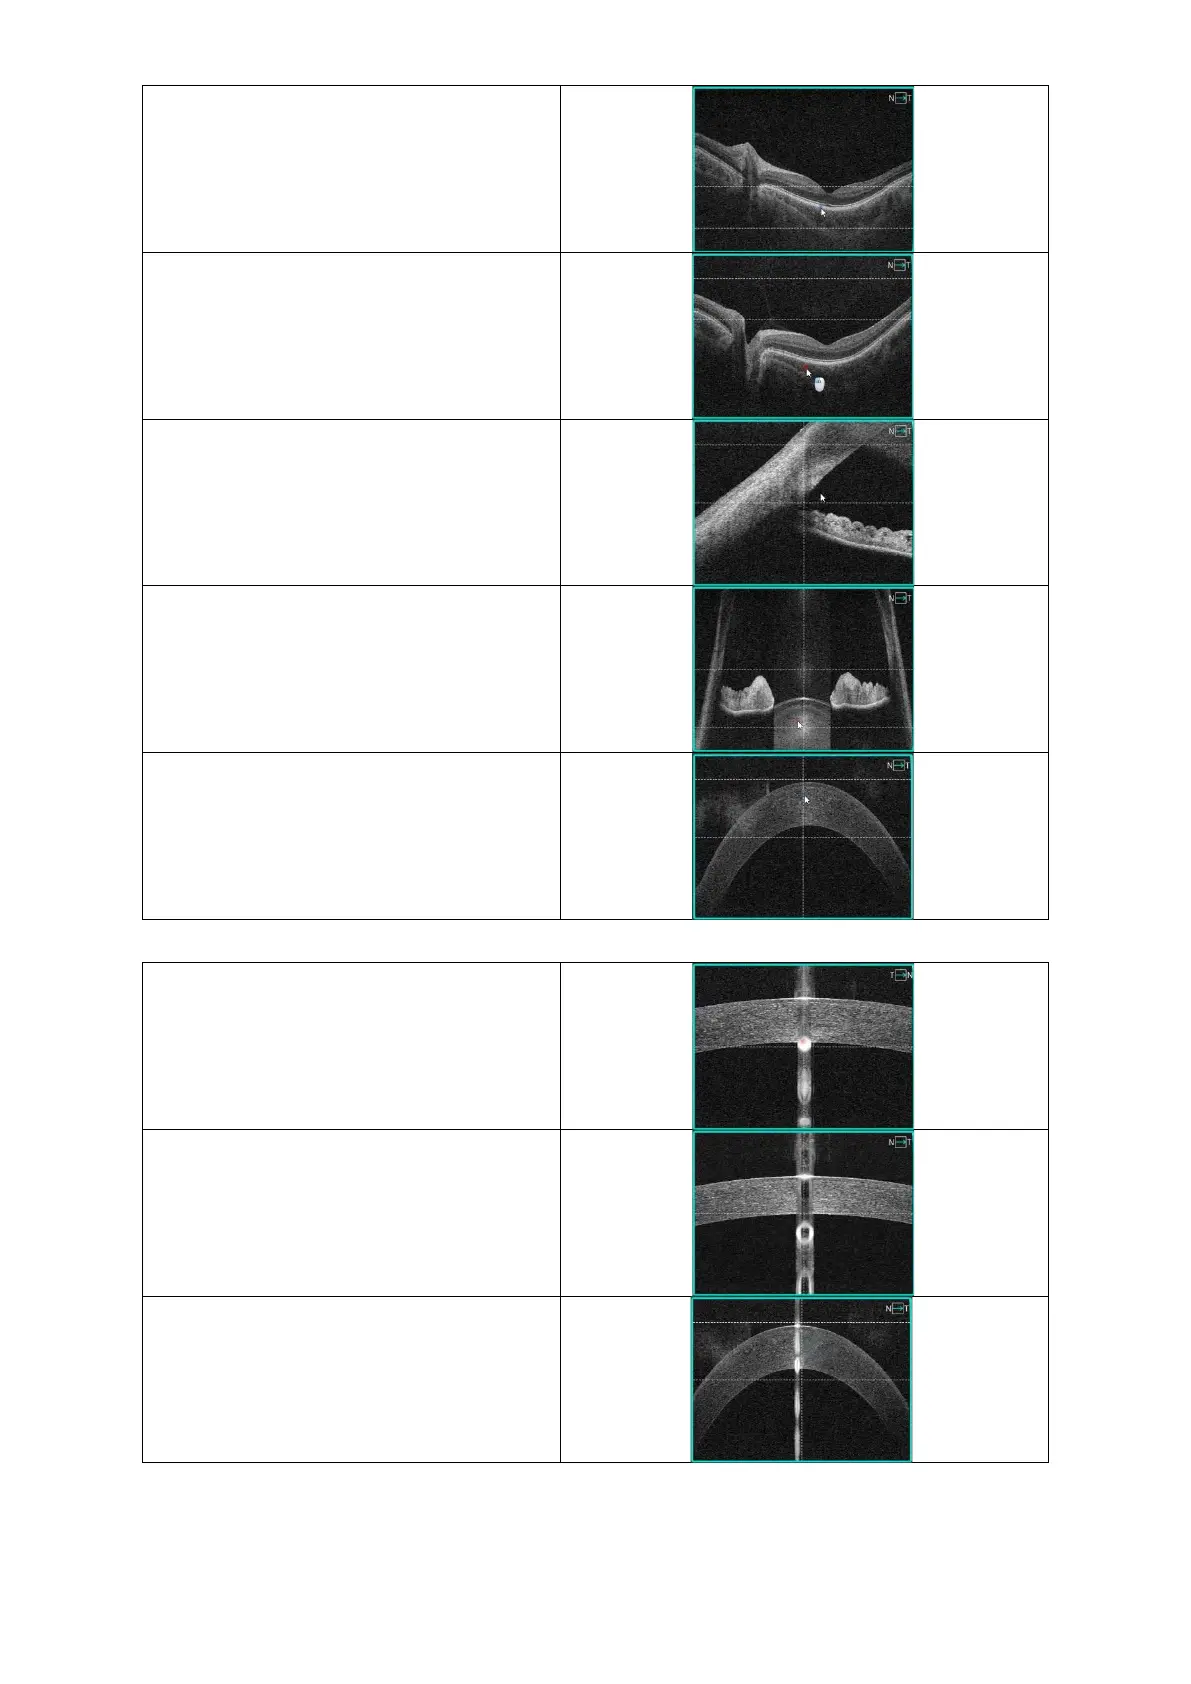

3D Central, align the retina between the

two dashed horizontal lines.

For all Vitreous scans, align the Vitreous

structure between the two dashed

horizontal lines.

Anterior B-Scan Angle C-Gate top, place

the angle structure below the dashed

Anterior Wide B-Scan with Two Angles,

align the two angles between the dashed

Anterior Wide B-Scan Cornea, align the

desired structure between the dashed

Biometry Axial Length, align the central

cornea reflexes with the dashed vertical

line.

Biometry ACD, align the central cornea

reflexes with the dashed vertical line.

Topography, align the desired structure

between the dashed horizontal lines and

the central cornea reflexes with the

vertical dashed line.